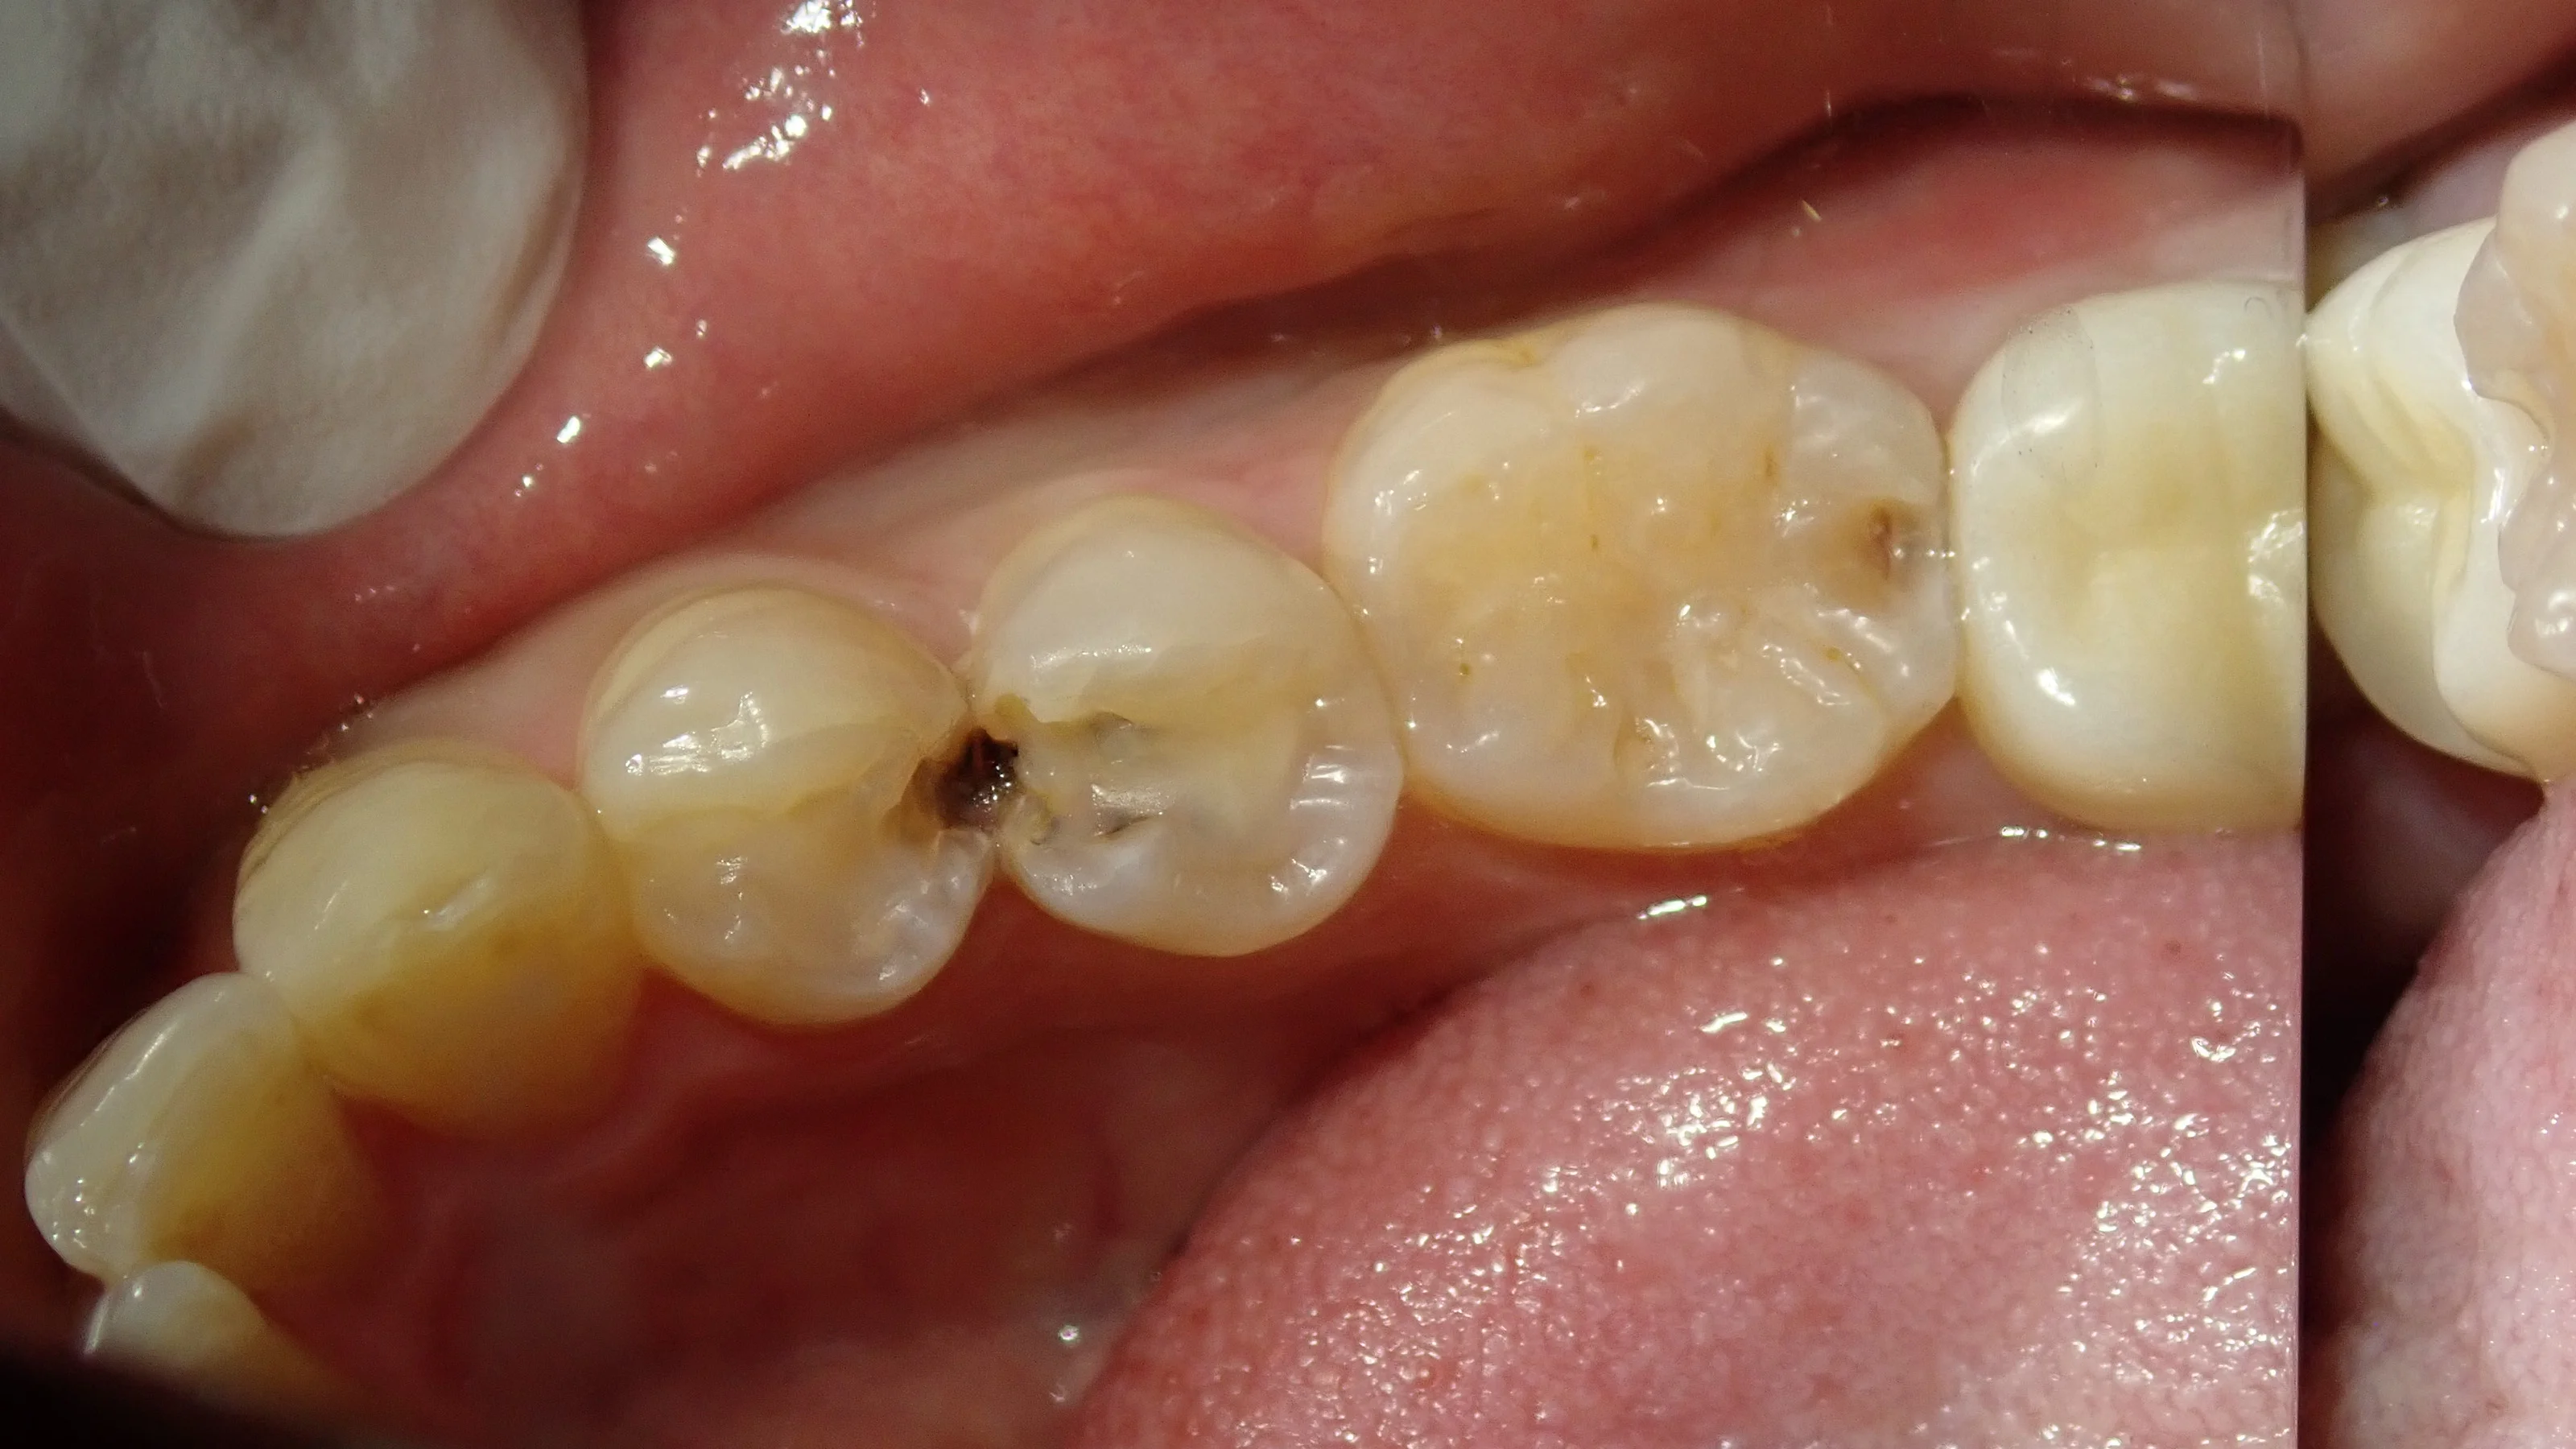

軽く古い詰め物を取ってみたのがこちらの写真です。

ここまで行くと真っ黒になっているのが分かりやすいですね・・・。